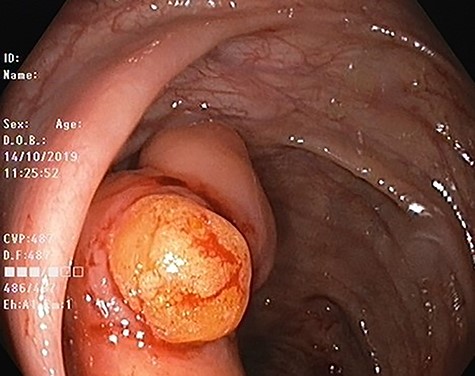

Our patient is 56-year-old female, a known case of locally advanced breast carcinoma. She was initially managed by chemotherapy followed by modified radical mastectomy then adjuvant radiotherapy and chemotherapy. The patient gave a positive family history of colon cancer; therefore, genetic testing for adenomatous polyposis coli (APC) mutation and surveillance colonoscopy were recommended by genetic counselor. The APC gene mutation came to be positive and as part of the work up for her primary disease, computed tomography (CT) scan of the abdomen performed and showed evidence of 4 cm intraluminal lesion in the ascending colon suggestive of lipoma without bowel obstruction (Fig. 1). As a result of these findings, colonoscopy was performed and it revealed a large smooth intraluminal subepithelial lesion in the ascending colon occupying one third of the lumen circumference (Fig. 2). With the use of biopsy forceps, indentation of the tumor can be seen, which is as known as “pillow sign” and once a biopsy taken, a fatty yellowish material was seen protruding from the biopsy site suggestive of lipoma (Fig. 3). Histopathological examination showed multiple fragment of normal colonic mucosa and fragments of mature adipose tissue consistent with lipoma (Fig. 4, black arrows). Clinically, the patient denied history of abdominal pain, rectal bleeding, changes in her bowel habit and intestinal obstruction symptoms. She denied any personal history of malignancy or lipoma. On physical examination, there was no evidence of any lipomas in particular her scalp, limbs or trunk. Although she has no gastrointestinal symptoms attributed to the lipoma, given that it is large in size and she is in clinical and radiological remission, we referred her for the opinion of colorectal surgery.

Colonoscopic image of ascending colon lipoma showing normal mucosa.

Endoscopically, colonic lipoma is recognized easily as a well-delineated, soft, round or ovoid, yellowish sessile or pedunculated mass. Although the mucosa overlying the lipoma is usually intact, however, in rare cases ulcerations and erythema can be seen on the mucosa, which may lead to impression of malignancy. Because of the lipomas’ location in the submucosa, three endoscopic signs may contribute to the diagnosis: the ‘cushion sign’ (probing the polyp with a closed biopsy forceps will often yield a pillow-like indentation), the ‘tenting effect’ (grasping the overlying mucosa with biopsy forceps presents a tent-like appearance), and the ‘naked fat sign’ (biopsies may result in an extrusion of yellowish fat) [4]. Endoscopic ultrasonography (EUS) can be used to distinguish lipoma from other submucosal lesions such as leiomyoma and schwannoma. On EUS, lipoma appears as hyperechoic lesions with regular borders in the three layers. EUS is also useful in the determination of a possible extension into the muscularis propria before attempting endoscopic resection.